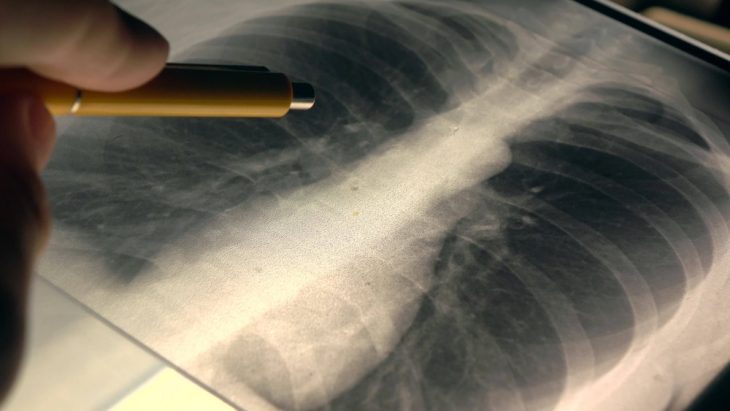

Для проведения рентгенографии органов грудной клетки в медицине применяют очень низкую дозу рентгеновского излучения. Проходящие сквозь тело лучи по-разному поглощаются тканями, в результате чего на пленке или экране формируется изображение легких, сердца, ребер, грудины и позвоночника.

Кости хорошо задерживают лучи, тогда как внутренние органы, мышечная и жировая ткани пропускают их. Поэтому-то изображение грудной клетки и выглядит как светлые кости, вокруг них серые мягкие ткани, а внутри – темные воздушные поля легких.

Врач-рентгенолог рассказывает и показывает, что видно на рентгенограмме органов грудной клетки в норме: